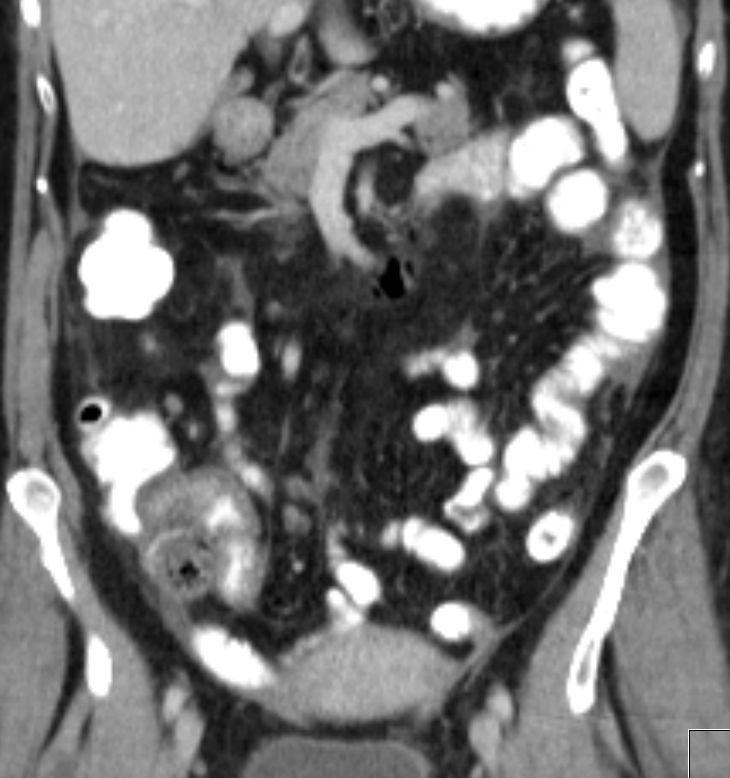

| Knochen | 81-jährige Patienten mit Endometriumkarzinom von

23 Jahren. Jetzt ossäre Metastase des vorderen rechten Schambeins mit

pathologischer Fraktur. Zystische Raumforderung dorsal seit 8 Jahren

unverändert.![]() | ||